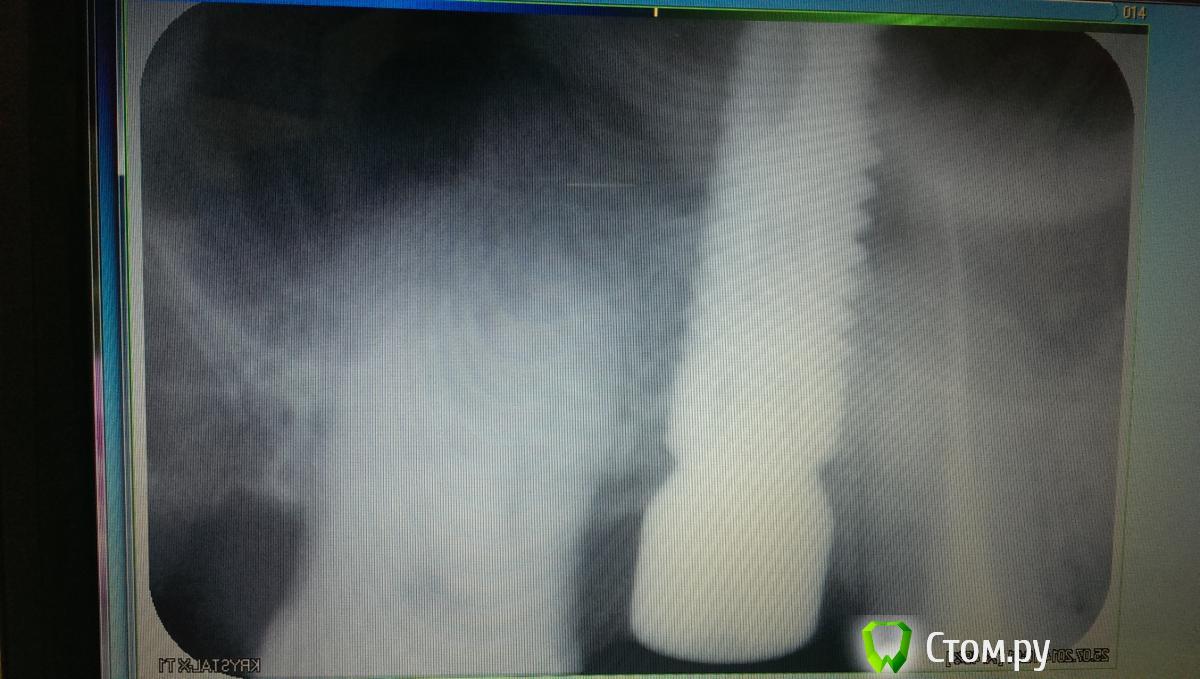

art700 Опубликовано 25 июля, 2014 Поделиться Опубликовано 25 июля, 2014 (изменено) Протезировать на имплантах начал недавно, такой вопрос возник пришёл пациент, в декабре поставили два импланта, 10 дней назад поставил фдм, снимок прилагается, фдм стоит практически на уровне десны, что делают в таких случаях? Изменено 25 июля, 2014 пользователем art700 Ссылка на комментарий

doc-евгений Опубликовано 25 июля, 2014 Поделиться Опубликовано 25 июля, 2014 (изменено) IMAG0200.jpgПротезировать на имплантах начал недавно, такой вопрос возник пришёл пациент, в декабре поставили два импланта, 10 дней назад поставил фдм, снимок прилагается, фдм стоит практически на уровне десны, что делают в таких случаях?Прикручивайте трансфер и снимайте оттиск! Ну может еще подождать немного если десна не созрела Изменено 25 июля, 2014 пользователем doc-евгений 1 Ссылка на комментарий

art700 Опубликовано 25 июля, 2014 Поделиться Опубликовано 25 июля, 2014 (изменено) Это понятно все. Я по поводу уровня десны, она не слишком низко?абатмент с коронкой сядут? Изменено 25 июля, 2014 пользователем art700 Ссылка на комментарий